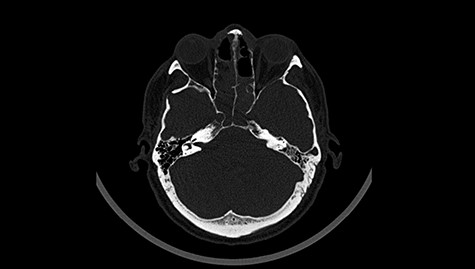

Head CT after polypectomy—seen sphenoid sinus and both maxillary sinuses filled with blood. (Department of Neurosurgery own material).

In described case, a head CT scan after polypectomy confirmed the subarachnoid hemorrhage (Fig. 1). In addition, the presence of air in the ventricular system was visible, and presence of defects of the upper left orbital wall and ethmoid on both sides (Fig. 3). In the CT scan sphenoid sinus, frontal and ethmoidal sinuses on both sides and right maxillary sinus airless, filled with blood and soft tissue. The changes also concerned the lateral part of the left maxillary sinus (Fig. 4).